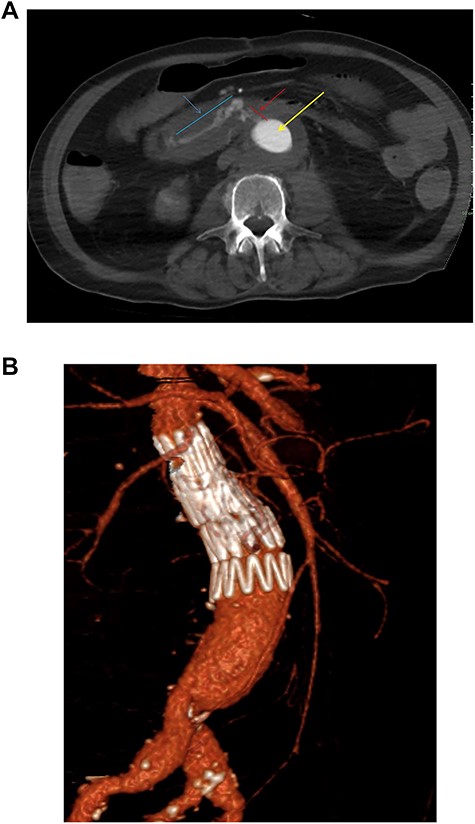

Fourteen months later, he presented to the emergency department with melaena and haemoglobin of 62 g/l. Following resuscitation an OGD was normal and CT angiography was unable to determine any definitive active bleed but suggested a possible AEF given the close proximity of the third part of duodenum to the aortic graft. Twenty-four hours later, the patient collapsed with a large amount of melaena and frank rectal bleeding in hemorrhagic shock. A new CT scan showed an AEF between distal right common iliac artery and ileum (Fig. 2b) not associated with the suture line of the previous open repair. Of note, this was found to be present on initial emergency imaging when reviewed by a specialist vascular radiologist.

(a) Preoperative coronal thick slice of a CT with IV contrast in the arterial phase shows aneurysmal aorta with normal calibre common iliac arteries; however, inflammatory change around the aortic aneurysm is seen extending into the proximal iliac bifurcation (blue outline); (b) axial slice of a CT with IV contrast in the arterial phase shows aneurysmal common iliac arteries (red arrow), a clear saccular bulge (blue outline) into an adhered loop of small bowel (orange outline and arrow); the site of the fistulation.